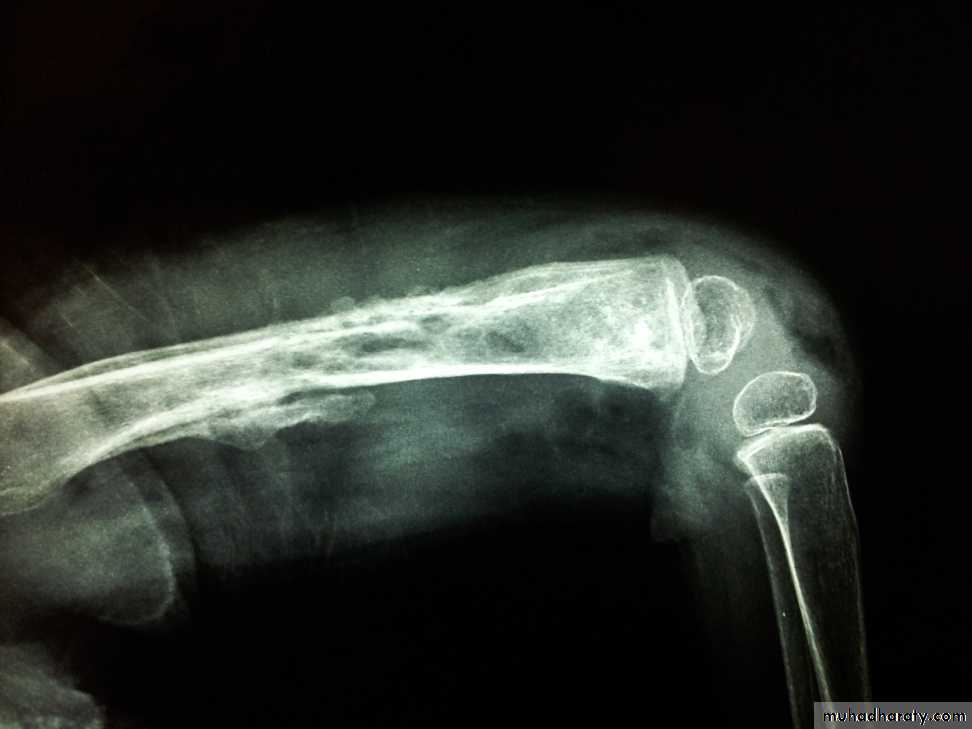

It is used to be a sequel of acute haemtogenous infection, but now it is more frequently follows open fracture or postoperative complication.Pathology:

There is destruction of bone that follows acute infection leaving sequestra surrounded by dense sclerotic bone.

The imprisoned sequestra provoke a chronic seropurulent discharge, that escape through a sinus. Bacteria may remain dormant for years giving rise to recurrent flare of acute infection.

Imaging:

X-Ray: shows area of rarefaction surrounded by sclerosis.

And sometimes with sequestra.